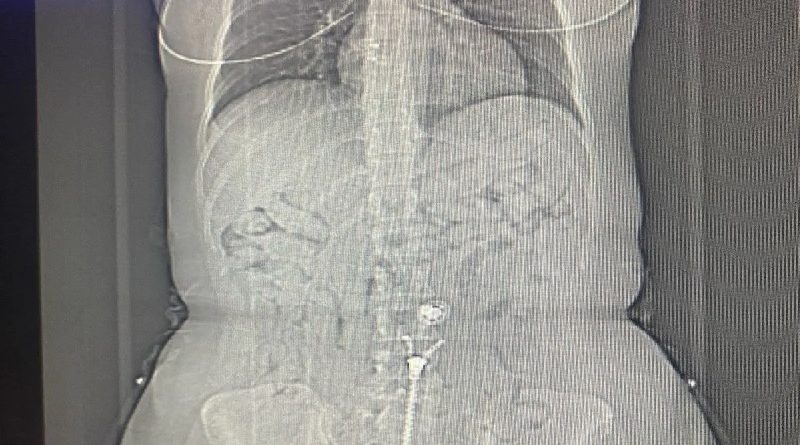

As mulheres foram retiradas do voo em Belém, por volta de 00h30 deste domingo. Em revista pessoal foram encontradas oito cápsulas de cocaína nos sapatos e dentro da roupa da brasileira. Se sentindo enferma, ela confessou ter cerca de 80 outras cápsulas no estômago, sendo conduzida até a emergência do Hospital Metropolitano de Belém, para expelir as demais cápsulas. Foram apreendidos 500 euros em posse da brasileira.